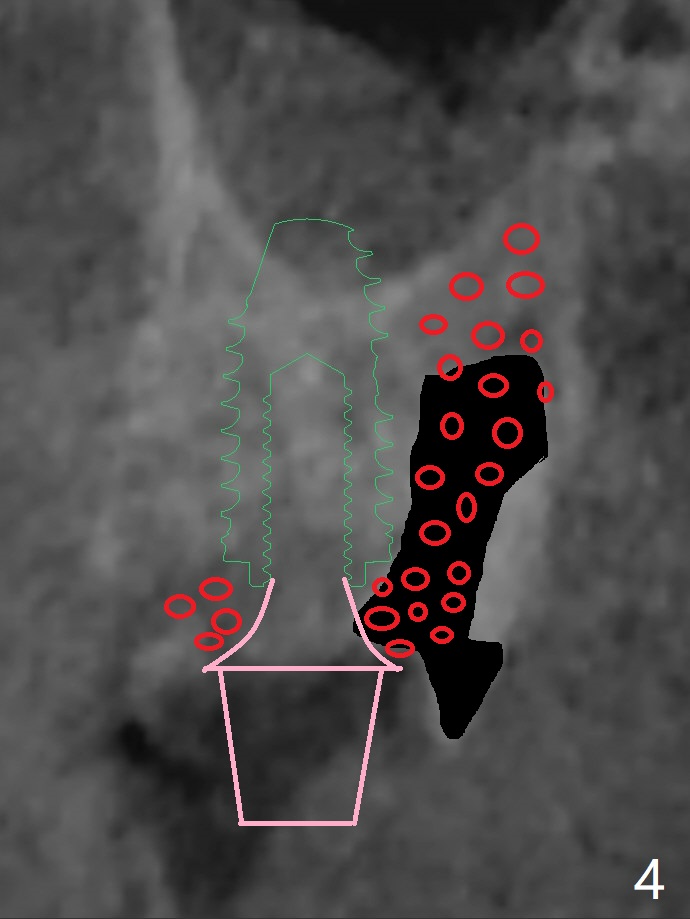

A 55-year-old man agrees to have the tooth #14 to be extracted for immediate implant. It appears that the palatal bone is lower than the buccal bone (Fig.1 arrowheads). If palatal shield is conducted (Fig.3 *), the implant can be longer (5x10 vs. 8.5 mm, Fig.2-4).